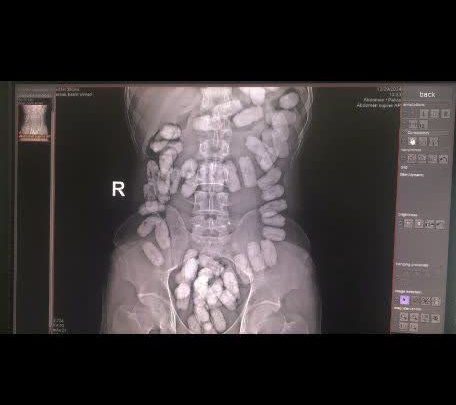

به گزارش صبح مشهد، سرهنگ “سیفی” در ادامه افزود: در راستای برخورد قاطع با قاچاقچیان مواد مخدر و جلوگیری از ورود مواد افیونی به داخل کشور، مرزبانان ایست و بازرسی ۱۷ شهریور در حین بازدید و بازرسی مسافرین در لاین ورود به کشور موفق شدند، تعداد ۴۸ بسته مواد آب بندی شده به وزن ۵۵۰ گرم موادمخدر از نوع هروئین پودری که در معده جاساز شده بود را از یک نفر تبعه افغان کشف کنند، که مواد و متهم تحویل مراجع ذی الصلاح گردیدند.